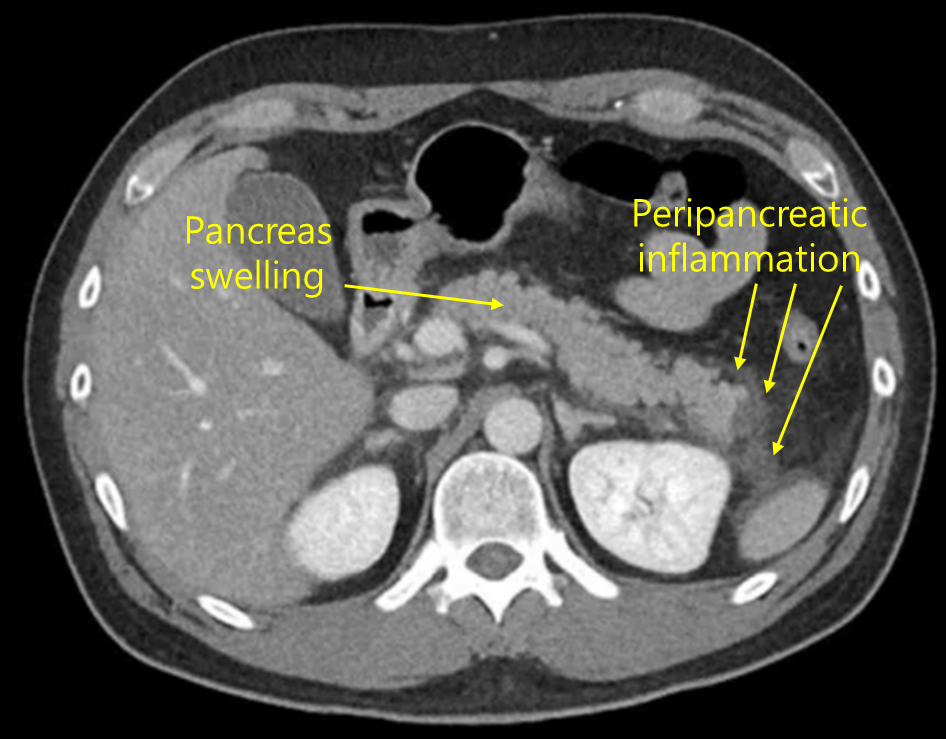

Img | CT: Pancreas swelling with peripancreatic fluid collection |

Epigastric pain, amylase/lipase elevation, CT상 확인되는 edematous pancreas 및 peripancreatic fluid collection으로 보아 acute pancreatitis로 진단한다.

• Amylase/lipase elevation이 정상상한치의 3배 이상인지는 명확하지 않으나, epigatric pain과 CT상 acute pancreatitis 양상을 보이므로 acute pancreatitis로 진단할 수 있다.

• 원인은 음주로 추정된다. AST/ALT elevation도 있으며 CT상 간이 매우 정상 간실질에 비해 매우 어둡게 조영되므로 alcoholic fatty liver, r/o alcoholic hepatitis도 동반되었음을 알 수 있다.

진단 | • US: 담석, 담관확장 확인 • CT: 췌장 실질의 edema, 췌장 근처 조직의 inflammation |